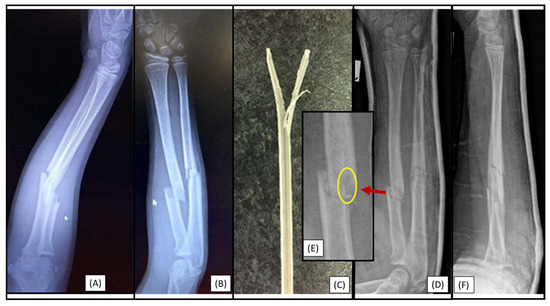

3.4. Case 4: Focal Medullary Cavity Stenosis